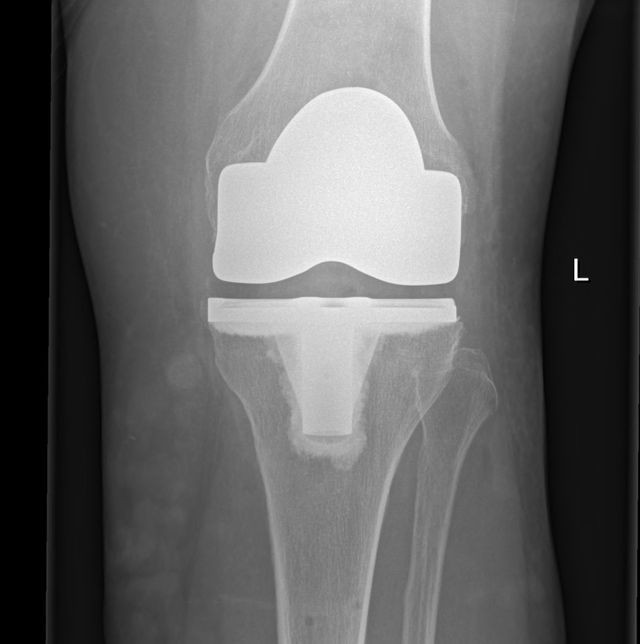

Total Knee Replacement (TKR) Dr A. Theodorides Knee Surgeon Specialist What Is The Best Pain Medication For A Total Knee Replacement Knee replacement surgery replaces a damaged knee with an artificial joint. After, you will need various medications to manage pain and prevent complications. Pain, swelling, and bruising can last for several weeks or even months after knee replacement surgery. Wearing compression stockings, keeping your legs elevated, and applying topical. You can also try massage,. Get your strength back more quickly;. What Is The Best Pain Medication For A Total Knee Replacement.